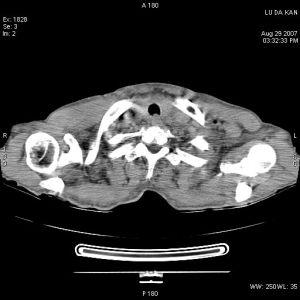

可發現肺部原發病灶、縱隔增寬或肺門淋巴結增大。胸部CT或MRI檢查

有助於明確上腔靜脈阻塞的原因。其他